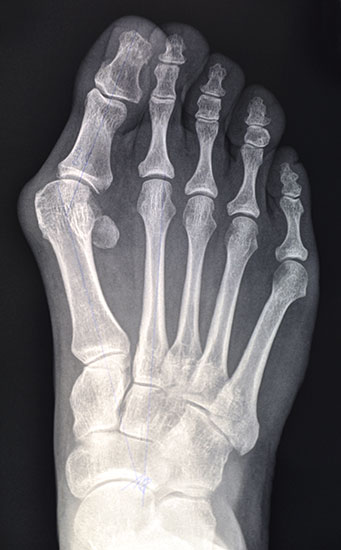

Die primäre Therapie von belastungsabhängigen Beschwerden im Vorfußbereich ist konservativ. Im Rahmen der Diagnostik werden Röntgenbilder des ganzen Fußes im Stehen angefertigt, um die statischen und funktionellen Verhältnisse des Vor- und Rückfußes zu beurteilen.

• Klinische Untersuchung, Anamnese, Bildgebung mit Röntgen des Fußes unter Belastung in mindestens 2 Ebenen.